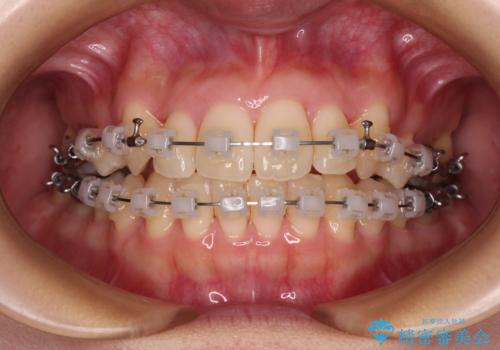

- クリアブラケット

- 1年11ヶ月

八重歯をスムーズに解消するために、補助装置を用いることで速やかに歯列を整えることができました。